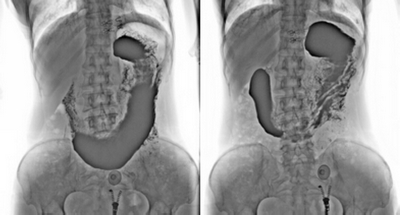

★消除普通數(shù)字胃腸機視野小的缺陷,直接獲得大視野全數(shù)字化圖像 (17x17) 。

★更加方便胃腸、食管、上消化道、全消化道等造影功能!

★各種普通及特殊造影,如口服膽囊造影、靜脈膽道造影、T管造影、逆行胰膽管造影(ERCP)、靜脈腎盂造影(IVP)、子宮輸卵管造影、脊髓造影等。